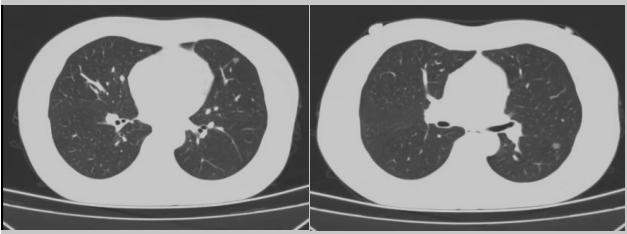

病例二:42歲的范女士,半年前體檢時(shí)發(fā)現(xiàn)雙側(cè)多發(fā)肺結(jié)節(jié),平時(shí)沒(méi)有什么不適。四個(gè)月后再次復(fù)查胸部CT,左上肺及下肺多發(fā)的磨玻璃結(jié)節(jié),其中下葉9mm的結(jié)節(jié)定為高危病灶。看到結(jié)果范女士坐不住了,多方打聽(tīng)慕名找到了市二院院長(zhǎng)王瑾,經(jīng)“肺結(jié)節(jié)MDT”團(tuán)隊(duì)會(huì)診后,決定手術(shù)治療。入院后,胸外科副主任醫(yī)師薛飛詳細(xì)與范女士溝通,并利用Mimics做好了術(shù)前肺部三維重建手術(shù)規(guī)劃,打消了范女士心中的顧慮。經(jīng)過(guò)前期充分準(zhǔn)備后,歷經(jīng)1小時(shí)30分,完成“胸腔鏡下左肺上葉舌段楔切及左肺下葉背段切除術(shù)”,術(shù)后病理檢查結(jié)果確診為左肺微浸潤(rùn)性腺癌。在胸外科團(tuán)隊(duì)的悉心照顧下,患者術(shù)后恢復(fù)良好,一周后順利出院。